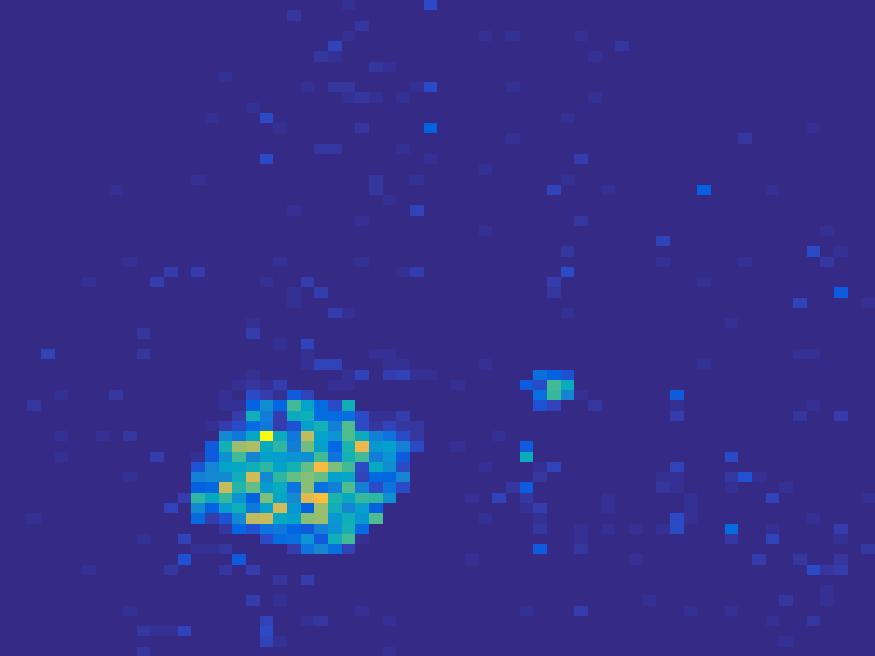

The proposed method is tested on numerical phantoms for a proof of concept study. We simulate image frames of size and projections per frame. Three time activity curves (TAC) for blood, liver and myocardium, previously used in [14] (see Figure 1), are used to simulate the dynamic images. The first simulated dynamic phantom is composed of two ellipses. In temporal direction, the positions of the two ellipses are stationary while the intensity in 90 frames within the region of each ellipse is generated according to the TAC of blood or liver. The projections are generated by using Radon transform sequentially performed for each frame.

In the tests, projections at two orthogonal angles are simulated for every frame to mimic 2-head camera data collection. The projection angles increase sequentially by along temporal direction. For example, at frame 1, projections are simulated at angle and , and at frame 2, angle and , etc. Finally, white Gaussian noise is added to the projection data. Reconstruction results with different methods are shown in Figure 3. Since the number of projections is very limited for each frame, the traditional FBP and least square methods cannot reconstruct the images satisfactorily, while the proposed method is capable to reconstruct the images effectively. Compared with SEMF model, when the edge of images jump (see frame 21 -frame 31 in Figure 3), the proposed model can better capture the change of the tendency of TAC.